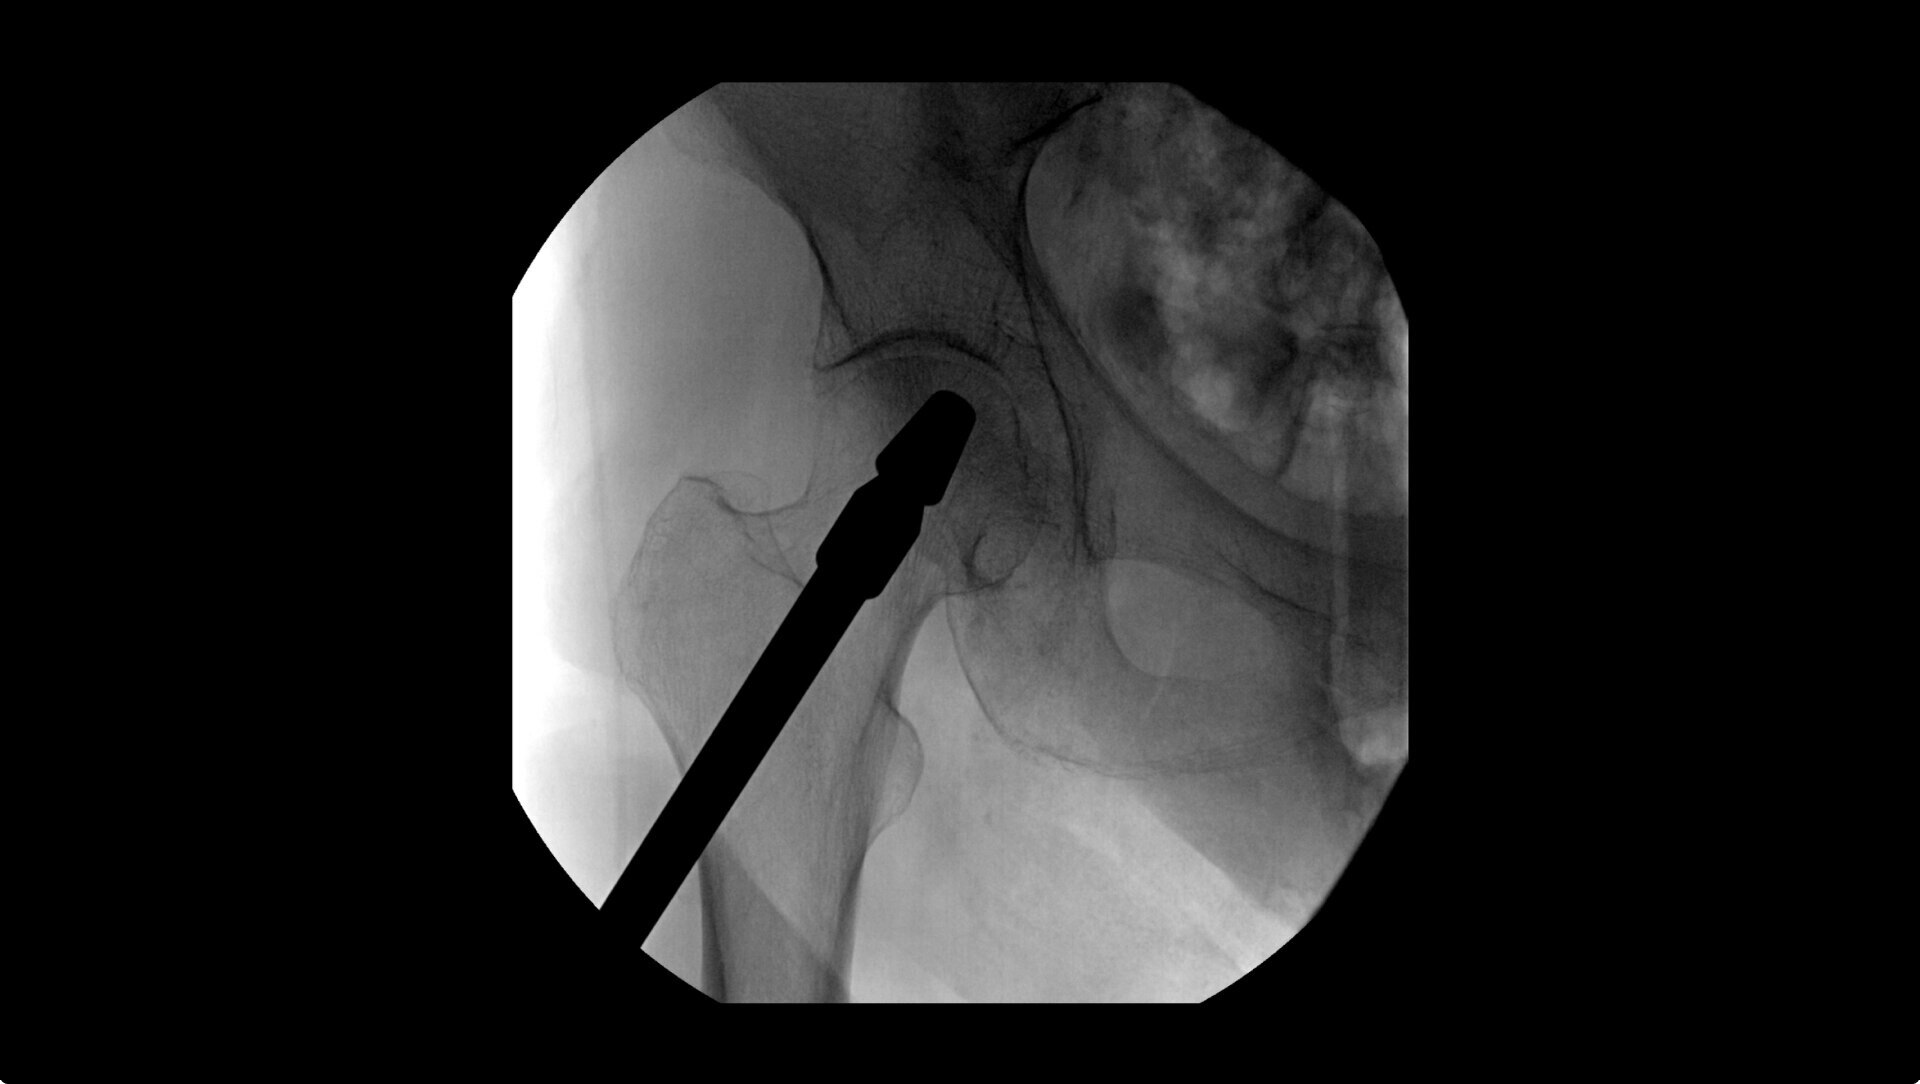

OEC C-arms provide orthopedic imaging with a large field of view optimized to clearly visualize orthopedic anatomy, such as the entire long bone femur or minute fractures in extremities. A clear display with comfortable viewing can easily show AP and lateral views, enabling efficient procedure planning.

During hip or femur imaging, capture up to 22% more Field of View by positioning detector closer to patient anatomy with the OEC low-profile X-ray tube housing compared to mono-block C-arms.

Complex orthopedic procedures require powerful imaging systems. OEC premium C-arms perform in a variety of procedures such as:

• Hip fracture fixation

• Hip replacement

• Shoulder fracture reduction